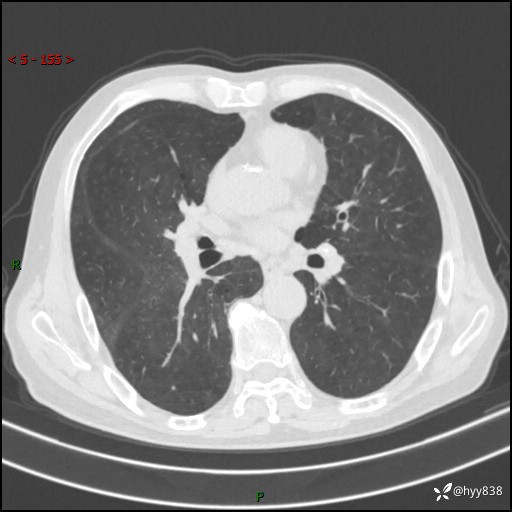

辅助检查:CT

胸部CT平扫